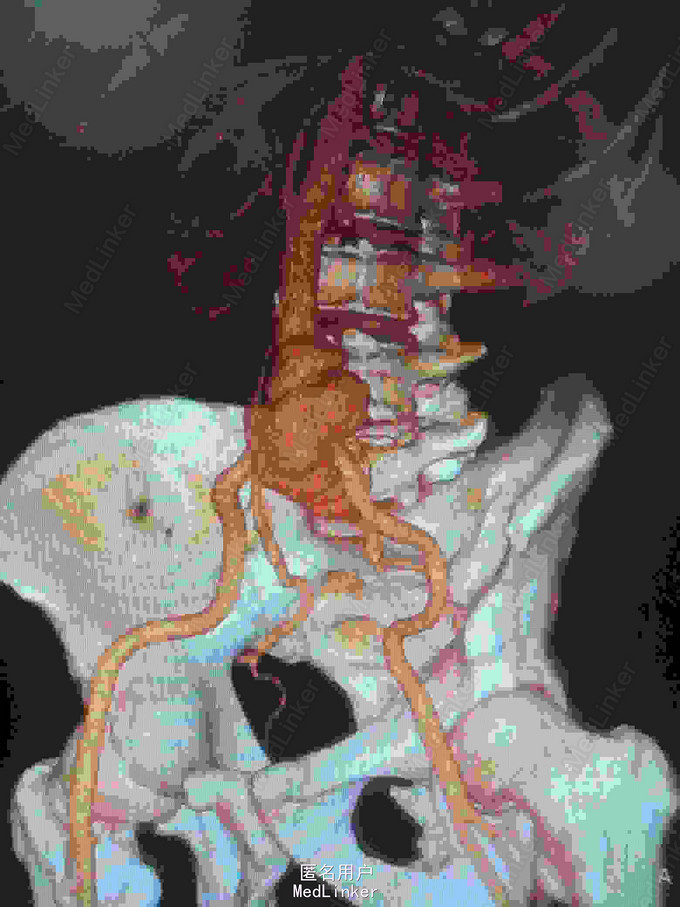

主诉:腰腹痛7月,加重一周。 病史:七月前发热后开始出现腰腹痛,呈持续性撕裂样痛,伴腹胀,症状反复。一周前腹痛症状加重。

体查:下腹部可触及搏动性包块。 辅助检查:腹部CT:腹主动脉假性动脉瘤并血栓形成,腰5椎体受侵蚀。血培养:沙门氏菌。

诊断:沙门氏菌感染性腹主动脉假性动脉瘤 处理:急诊行腹主动脉瘤切除人工血管置换术,术后予美罗培南抗感染8周,续以左氧氟沙星口服。